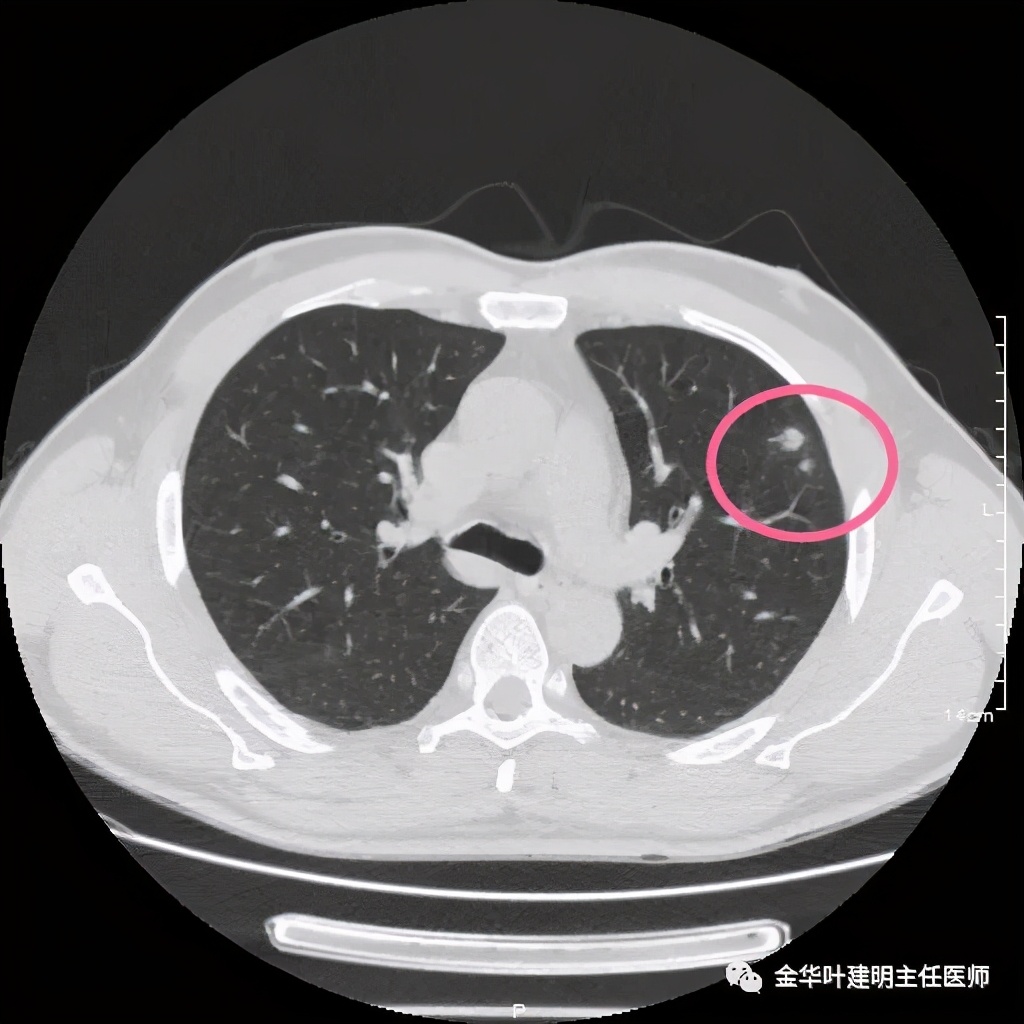

患者为48岁男性,检查发现左肺上叶实性结节,临床没有炎症表现,肿瘤指标不高,没有查过结核及隐球菌荚膜抗原试验或G试验、M试验等。我们先来看其前一个月时的平扫影像:

上图示有血管征,与病灶关系较密切

上图示血管与病灶临近,但没有被病灶牵拉从而进入病灶

我们见左上实性病灶,主病灶旁有卫星灶,有血管进入,但也有贴边走行,边缘略显模糊,膨胀感与细毛刺不明显,收缩力也不明显。下面是其靶扫描的片子: